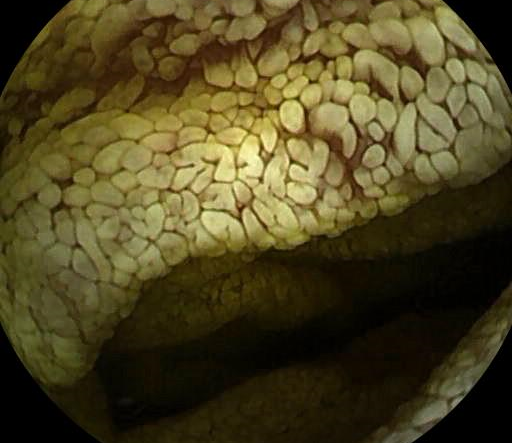

The gleaming bowel behind chronic diarrhea

João Correia, Maria Manuela Estevinho, Pedro Mesquita, Adélia Rodrigues, Rolando Pinho, Ana Ponte, Teresa Freitas

Centro Hospitalar de Vila Nova de Gaia/Espinho

A 61-year-old woman was under investigation due to a three-year clinical condition of polyarthralgia, unexplained weight loss, watery diarrhea and iron-deficient anemia. Upper endoscopy revealed a whitish duodenal mucosa, which was biopsied. Small bowel capsule endoscopy was also performed, revealing a diffusely congestive and whitish duodenal and jejunal mucosa, suggestive of Whipple Disease. Histological results later confirmed the presumptive diagnosis and the patient started on antibiotherapy, with progressive improvement of her clinical condition.